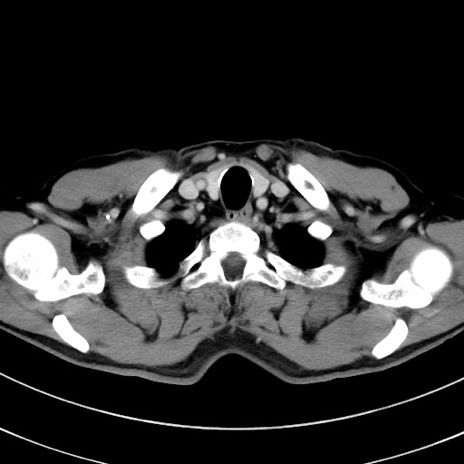

症例8(横断像)

【症例】 60歳代男性

【主訴】 黒色吐物

【現病歴】 4日前から嘔気自覚、2日前の朝食後にも嘔気あり、自分で手で嘔吐反射起こし嘔吐したところ血が混ざっていたため受診。

【既往歴】 5年前汎発性腹膜炎を伴う急性虫垂炎で手術、高血圧、前立腺肥大症、高脂血症

【身体所見】 腹部正中に手術癩痕あり 腹部平坦・軟圧痛なし膨満感あり

【データ】WBC 8400、CRP 4.54